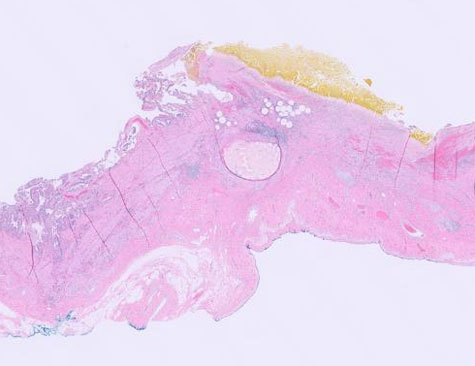

The patient had persistent disease identified on post-treatment imaging and was offered resection. Intraoperatively, the liver appeared to be cirrhotic with abdominal stigmata of portal hypertension. An abnormal appearance of the gallbladder infundibulum and neck was noted, a thick white appearance with a palpable mass. The gallbladder was resected and sent to the pathology unit for a frozen section to rule out metastatic disease. The palpable mass in the gallbladder which was noted to be consistent with a gall stone and the hard white area was consistent with chronic inflammation with embolic beads. Though there was suspicion of metastasis based on the gross appearance of the gallbladder, the final postoperative pathological diagnosis revealed cholelithiasis and chronic cholecystitis with chemoembolization beads with no carcinoma, as shown in Figure 1, Figure 2, Figure 3.

Figure 2: Pathology slide of gallbladder without evidence of carcinoma.

Figure 3: Pathology slide of gallbladder without evidence of carcinoma.